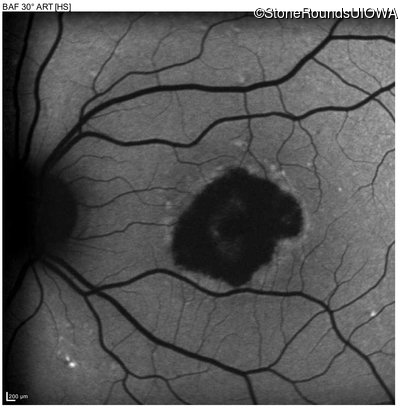

Infrared Fundus Photograph - Left - 20/200 -1

Exemplar